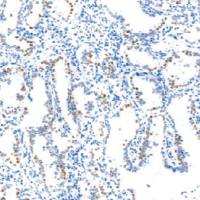

应用:WB,IHC-P

Human,Mouse,Rat - Application

WB,IHC-P - Dilution Ratio

WB: 1/500-1/1000 IHC: 1/50-1/100 - Molecular Weight

文献和实验Phospho-Tau (Ser396) Antibody 是一个非偶联、分子量约 79 kDa、兔源、抗磷酸化 Tau(S396) 单克隆抗体。它可用于小鼠、大鼠、人背景下 WB、ICC/IF、IHC-P 实验,且不带标记。